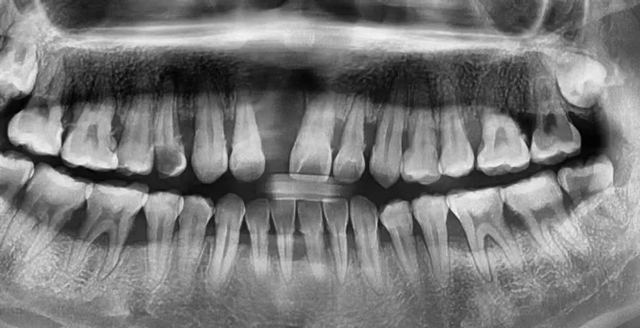

日前,新桥口腔接诊了一位网购牙套自行矫正的95后女生,因自小受“地包天”困扰,两年前,爱美心切的李蕊(化名)在网上花费几百元心动下单“定制版隐形牙套”并坚持佩戴,虽然牙齿反颌问题确实得到改善,可更多的问题接踵而至:牙齿一咬就疼,全口牙齿松动,连门牙都脱落了!医生检查发现,她的牙槽骨已被吸收破坏,且不可逆。

李蕊口腔全景片